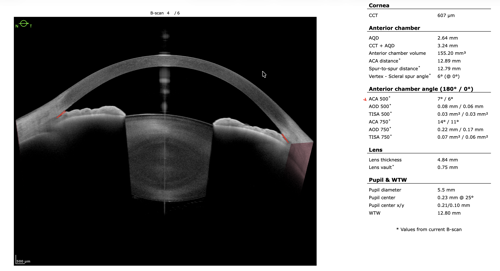

To refine surgical candidacy, anterior segment imaging was performed using the Heidelberg ANTERION SS-OCT. High-resolution imaging clearly demonstrated the following:

- A visually clear crystalline lens, not meeting criteria for cataract extraction

- Markedly narrow angles at iris insertion

- Angle measurements in the single-digit degrees

These findings supported LPI as the most appropriate intervention.